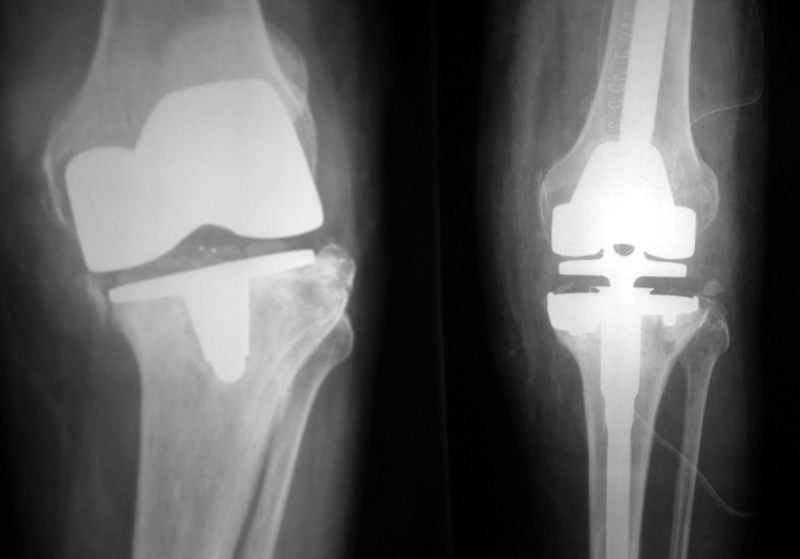

The company ORTHOPEDIC NIKIFOROV was founded in 1998 by the candidate of medical sciences. doctor of orthopedic-traumatologist of the highest category Nikiforov IA Owing to high professionalism and results of work, ORTONIC has gained well-deserved reputation and reputation among colleagues and population of Dnepropetrovsk region and CIS countries (Russia, Moldova, Armenia, etc.). The principle of the enterprise is NO IMPOSSIBLE, it is based on knowledge, experience and active implementation of modern technologies in orthopedics and traumatology. Conservative methods of treatment include individual selection of medicines, therapeutic blockades, manual therapy, massage, physiotherapy (vibration table, magnetotherapy, bioptron, electromyostimulation, etc.), rehabilitation with the suggestion of the necessary concomitant devices and means for the fastest recovery (corsets, bandages, various joint fixators, crutches, walking sticks, etc.). Various minor invasive interventions (chymonucleolysis, vertebroplasty, kyphoplasty, percutaneous nucleoplasty using cold plasma) that are performed on an outpatient basis are successfully used to treat problems associated with spine pathology. The latest modern treatment methods introduced in our company are endoscopic operations using the TYSSES technique of Joimax (Germany) with intervertebral hernias, stenosis and other pathologies of the spine, which allow to avoid complications occurring during open operations and the accompanying general anesthesia. We have many years of successful experience in traditional and modern minimally invasive endoprosthetics of large and small joints, which remains the main direction of our activity. Our company is the exclusive representative of the German company IO International Orthopaedics Holding GmbH, which based on the already known prostheses, its ideas and technological capabilities, has developed and implemented a new concept in hip replacement - an artificial joint prosthesis (ICON). We assist interested colleagues in training the operative technique for installing an artificial joint prosthesis - ICON, both in the workplace and in Germany. For 20 years we have been successfully cooperating with Sanitatshaus Gerd Klinz ortho team, an enterprise that for 20 years has been one of the leading places in Germany for the production of functional prostheses of the upper and lower limbs, as well as cosmetic prostheses of limbs and other body parts (nose, ears, eyeballs, fingers). We have an atmosphere of friendliness and human participation. Politeness, benevolence, the desire to understand and help is the basis of our attitude towards patients. We are always glad to see you and will do our best to make you feel great! We are waiting for you at: Ukraine, Dnepr, Gagarin Ave., 13 (under reconstruction) on all questions to address: tel .: +38 (050) 488-88-92 E-mail: orthonik.ukr@gmail.com Germany, Spine Nano Klinik, Zeppelinstr. 21, Potsdam Tel. +4901801121919 E-mail: kmw.nikiforov@hotmail.de